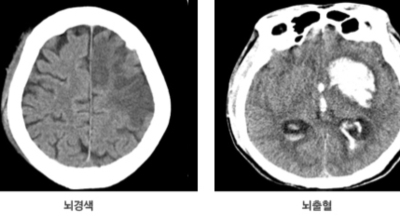

뇌출혈 전조증상을 놓쳐 뇌출혈이 발생하게 되면 발작 직후 안정을 취해야 합니다. 뇌부종을 가라앉히기 위해 약물 요법으로 고농도 포도당, 덱사메타존, 만니톨 등을 투약할 수 있고 뇌의 혈액 순환을 회복시키는 주사와 지혈제, 진정제 등을 사용할 수 있습니다. 혈종의 크기가 중등도 이상으로 마비 증세가 있으면 머리뼈에 작은 구멍을 내서 관을 넣어 혈종을 뽑아내는 수술을 시행할 수 있습니다.

혈압성 뇌출혈인 경우 혈종의 크기가 작으며 환자의 증상이 경미하면 약물 치료를 시행합니다. 혈종의 크기가 매우 크며 뇌가 심하게 부어오를 때는 응급으로 머리뼈를 절개해 혈종을 빠르게 제거해야합니다. 응급조치가 늦어지면 뇌압이 상승해 의식을 잃고 사망에 이를 수 있기 때문인데요 이렇게 증상이 심할 때는 수술이 잘 되었더라도 예후가 좋지 못할 때가 많다고 합니다.